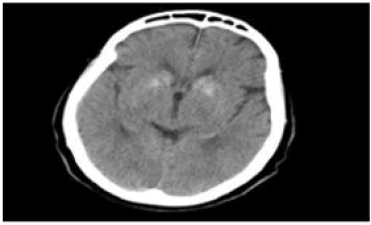

Our case was a 72-year-old woman with a history of thyroidectomy due to nodular goiter was treated with levothyroxine for 15 years ago. The patient has not had regular medical visits. She has had Parkinson's movements for 5 years ago. She has also had paresthesias around her mouth and hands for 1 year ago, which have not been investigated. The patient went to the emergency room due to decreased consciousness and convulsive movements and was admitted to the hospital because of profound hypocalcemia. The tests performed for the patient were as described in Table 1. The patient was diagnosed with iatrogenic hypoparathyroidism and in the brain CT (Figure 1), she had basal ganglia calcification, which was the cause of Parkinson's disease in this patient.